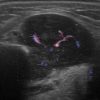

U tuyến nước bọt

» Thông tin: Nam giới – 63 tuổi.

» Lâm sàng: Khối vùng góc hàm.

# Lymphoma tuyến nước bọt dưới hàm.